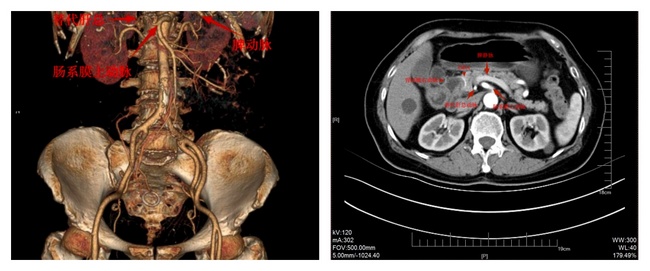

鄭磊參賽的《完全腹腔鏡下胃癌根治術(shù)——肝總動(dòng)脈缺如一例》,其難點(diǎn)一是在于對(duì)外科手術(shù)解剖的熟知與正確辨認(rèn)。正確的解剖是外科手術(shù)成功的基礎(chǔ),肝總動(dòng)脈是腹腔動(dòng)脈的主要分支之一,分為肝固有動(dòng)脈和胃十二指腸動(dòng)脈,負(fù)責(zé)向肝臟、胃、十二指腸等器官輸送富含氧氣的動(dòng)脈血,是肝臟供血的重要來(lái)源之一。因胚胎發(fā)育等因素,極少數(shù)人可能出現(xiàn)肝總動(dòng)脈缺如,而改由鄰近的血管供血,本例患者即由腸系膜上動(dòng)脈直接分為肝固有動(dòng)脈和胃十二指腸動(dòng)脈(如圖示)。如果術(shù)中未能清楚辨認(rèn),可導(dǎo)致術(shù)中大出血,或誤傷肝臟供血血管,可能導(dǎo)致術(shù)后肝功能受損,甚至出現(xiàn)術(shù)后肝功能衰竭,影響患者術(shù)后康復(fù)。另外動(dòng)脈血管的變異,還可能會(huì)影響淋巴結(jié)的清掃,因腹腔淋巴結(jié)多伴隨相應(yīng)的動(dòng)靜脈,若未能事先正確辨認(rèn),會(huì)影響手術(shù)清掃淋巴結(jié)的邊界與范圍,而淋巴結(jié)清掃則是胃癌根治手術(shù)的關(guān)鍵,可直接影響患者的預(yù)后和遠(yuǎn)期生存效果。

肝總動(dòng)脈缺如,由腸系膜上動(dòng)脈發(fā)出肝固有動(dòng)脈